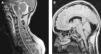

Síndrome de locked-in. Una mirada a su tratamiento y pronóstico

El síndrome de locked-in (SLI) se presenta con una cuadriplejia y anartria, con preservación de consciencia. Es decir, una falta de movilidad de las cuatro extremidades y la incapacidad neurológica para hablar. Presentamos un caso de SLI de origen traumático con el objeto de conocer las posibilidades de tratamiento y pronóstico, efectuamos una revisión de la evidencia disponible a través de la búsqueda con los buscadores PubMed y Trip Database. Las palabras claves utilizadas fueron: locked-in syndrome, rehabilitation, treatment y prognosis. Encontramos 28 artículos en relación con el tratamiento y 162 que trataban el tema del pronóstico.